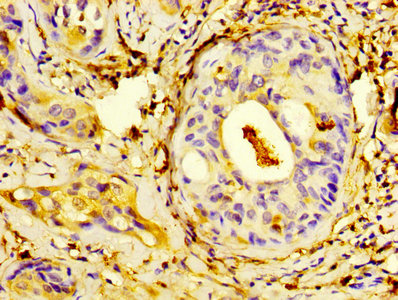

IHC image of CSB-PA020642HA01HU diluted at 1:400 and staining in paraffin-embedded human cervical cancer performed on a Leica BondTM system. After dewaxing and hydration, antigen retrieval was mediated by high pressure in a citrate buffer (pH 6.0). Section was blocked with 10% normal goat serum 30min at RT. Then primary antibody (1% BSA) was incubated at 4°C overnight. The primary is detected by a biotinylated secondary antibody and visualized using an HRP conjugated SP system.